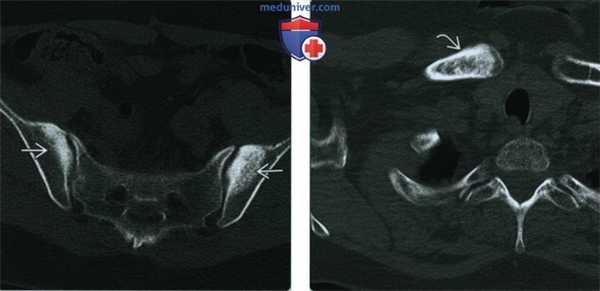

(Слева) КТ, аксиальный срез: у этой же пациентки подтверждается расположение склерозированной области в пределах крыльев подвздошных костей и щажение крестца и крестцово-подвздошных сочленений. Дополнительная визуализация или дальнейшее наблюдение при конденсационном остеите не требуются.

(Справа) КТ, костное окно, аксиальный срез: у пациента с болью выше правого грудинно-ключичною сочленения определяется диффузный склероз головки правой ключицы. Грудина (изображение не представлено) сохранна. Других поражений скелета выявлено не было. Ведущим предварительным диагнозом является конденсационный остеит ключицы.